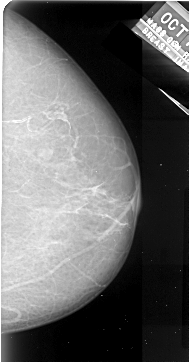

A_1006_1.LEFT_MLO

LEFT_MLO LINES 5461 PIXELS_PER_LINE 3256 BITS_PER_PIXEL 16 RESOLUTION 42 OVERLAY

FILE: A_1006_1.LEFT_MLO.OVERLAY

TOTAL_ABNORMALITIES 1

ABNORMALITY 1

LESION_TYPE MASS SHAPE IRREGULAR MARGINS ILL_DEFINED

ASSESSMENT 4

SUBTLETY 5

PATHOLOGY MALIGNANT

TOTAL_OUTLINES 1

BOUNDARY